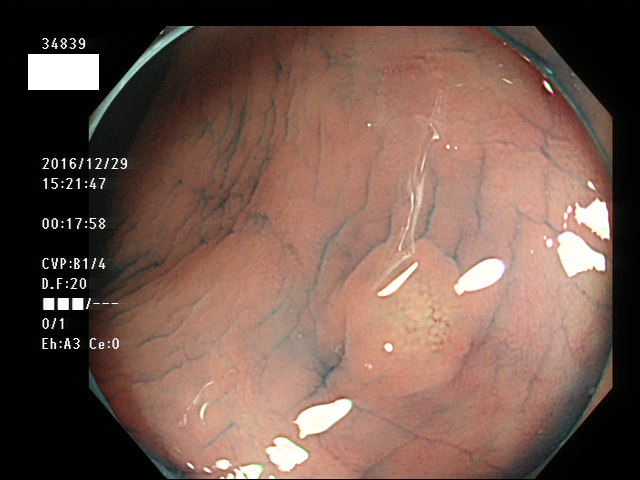

下記の写真は全て、当院で診断された微小カルチノイド(悪性)ですが、いかに診断が困難かお分かりいただけるでしょう。このような微小病変でさえも見落とせば人工肛門の危険が潜んでいる訳です。